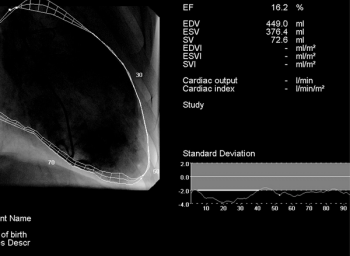

Empagliflozin (Jardiance; Eli Lilly) met the primary end point of a study for adults with heart failure with reduced ejection fraction with or without diabetes.

Data showed that empagliflozin with standard of care was superior to placebo in reducing the risk of CV death or hospitalization.